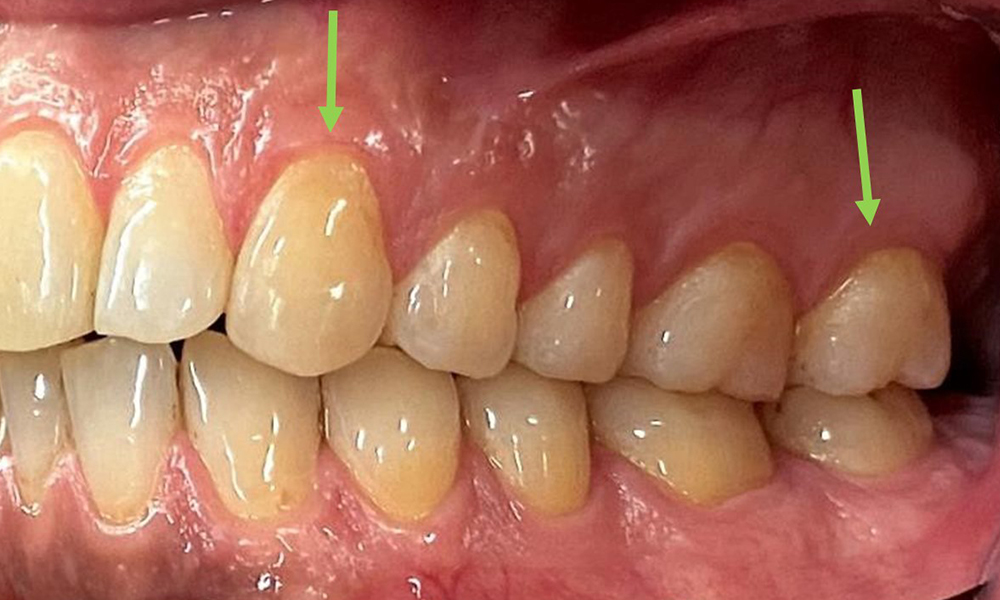

There were no pathological extraoral findings. During intraoral examination, inspection of the frontal view revealed brownish discolouration near the keratinised gingiva and at the transition to the moveable mucosa (Fig. 2), which could be attributed to nicotine consumption. Whitish mucosal lesions were observed on the palate, particularly near the maxillary molar palatal surfaces, indicating increased keratinisation and can also be attributed to nicotine consumption. The tongue was covered with a removable white and brownish coating.

The patient has full dentition with a total of 28 teeth. There were noteworthy erosions and attritions. (Fig. 4, Fig. 5). Due to bruxism, the patient has been wearing a splint with an adjusted bite block at night for many years. The erosions were caused by long-term consumption of isotonic beverages. No periodontal bone loss or active caries were observed.

At 1 to 3 mm, the clinical probing depths were within the physiological range. Maxillary recessions of up to 1 mm were observed from 13 to 16 and 23 to 27. The BOP was 15%.

Fig. 5: Close-up view of teeth 45 to 47. The green arrows show dental attrition and erosions of the buccal cusps with partial enamel loss, © Dr R. Krapf